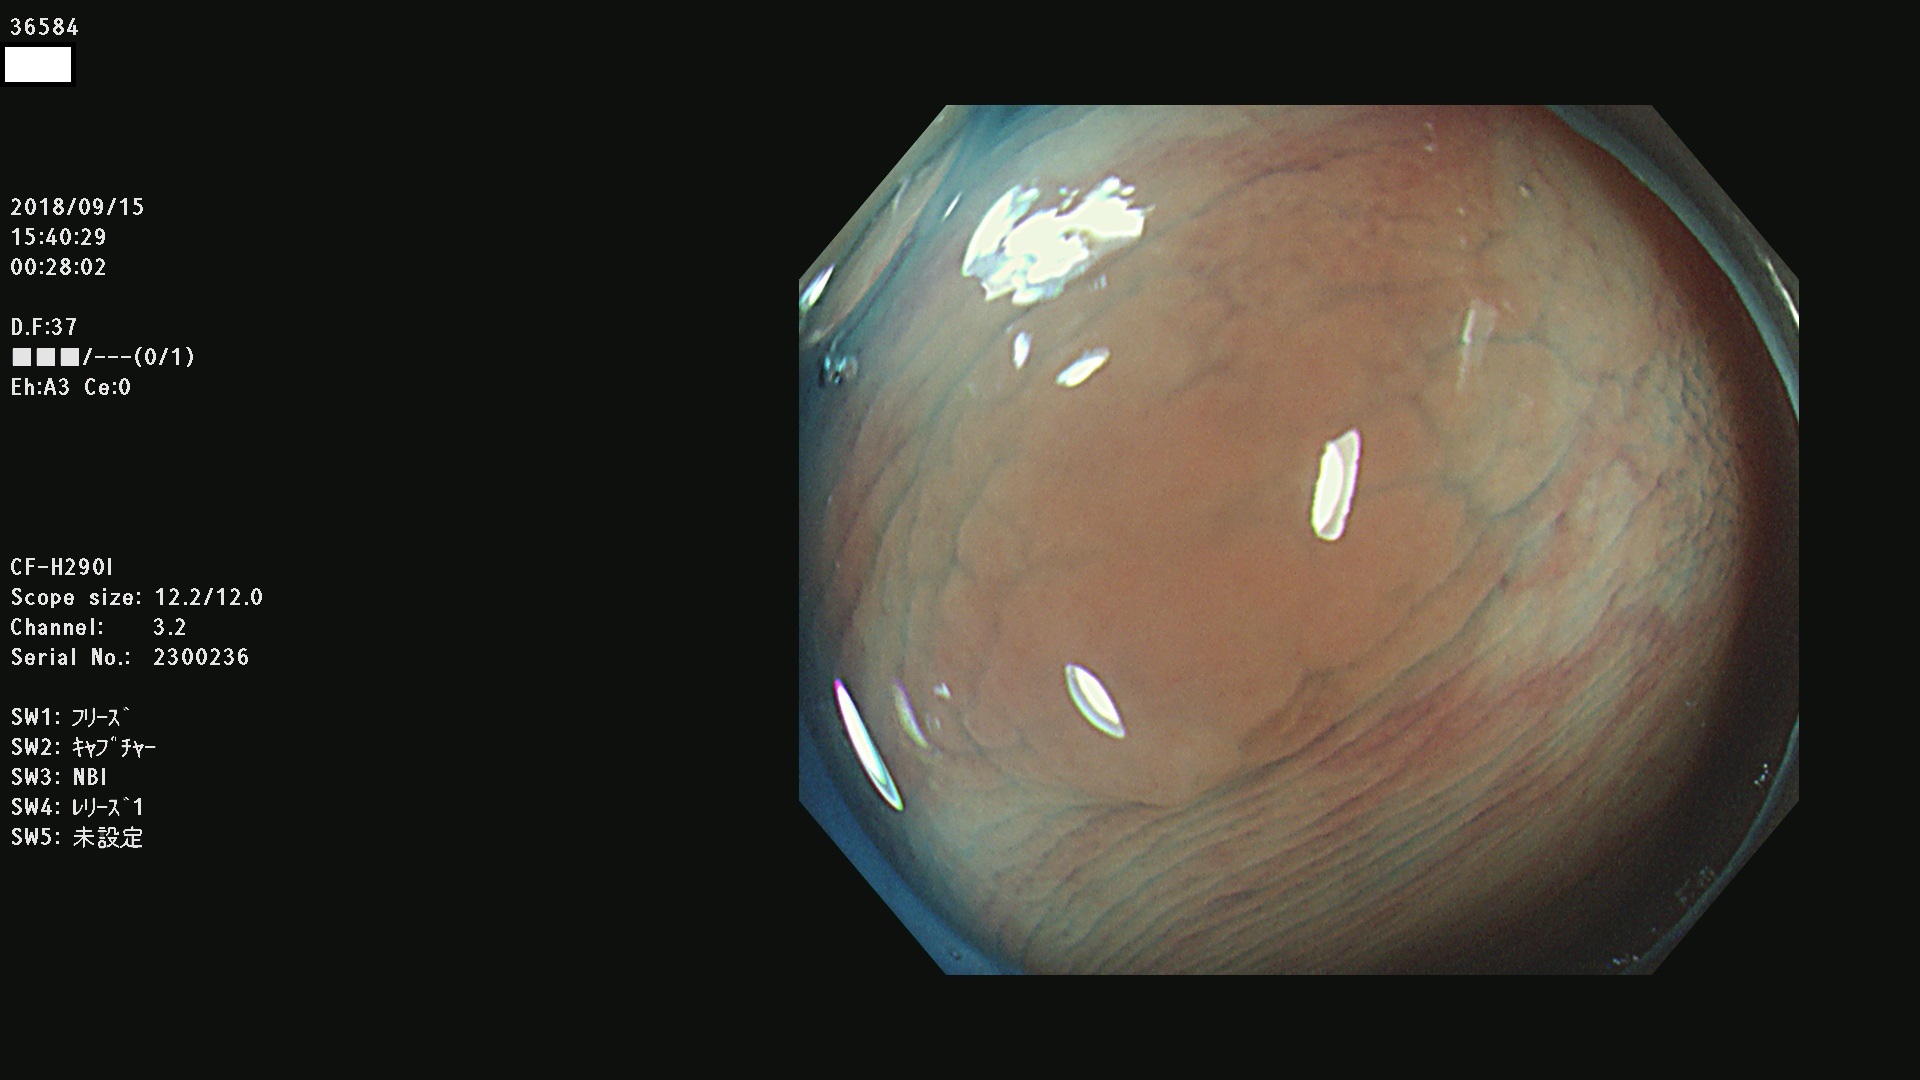

36500 36503 36504 36505 36507(SSAPのみ) 36508 36509 36510 36511 36514 36515 36517 36518 36520 36522(SSAPのみ) 36523 36524 36526 36528 36530 36531 36532 36533 36534 36535 36536 36538 36541 36542 36543 36544 36545 36546 36548 36550 36551 36554 36555 36556 36558 36559 36560 36561 36564 36565 36567 36568 36570 36572 36573 36574 36575 36576 36577 36578 36579 36580 36582 36584 36586 36591 36592 36593 36594 36595 36596 36597 36598

発見困難で危険性の高い平坦型病変(上記100名より抽出)